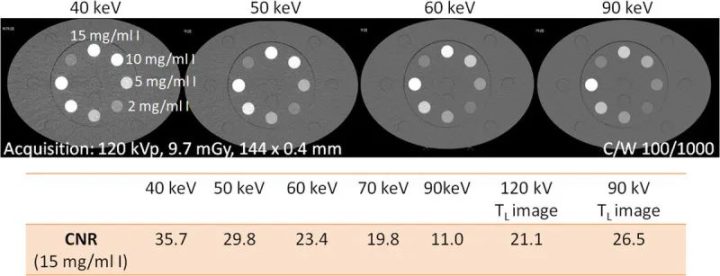

第一代临床PCD-CT采用了一种方法,为所有常规造影剂增强检查提供120 kVp或140 kVp的标准化采集协议。每次CT扫描的主要图像输出是根据临床问题量身定制的KeV水平的VMI,例如,用于实质器官成像的是60-65 keV,或用于CT血管造影的是45-55 keV。VMI的碘CNR可通过改进算法得到改善,使其随着keV的降低而增加,就像用较低的管电压(kVp)采集图像一样,见图9。这种方法能更好地实现CT图像结果的标准化,因为VMI中的碘对比度只取决于所选的keV水平,而与采集条件(尤其是X射线管电压)无关。

图9 将装有15mgI/ml溶液的管子插入大型(40×30cm)Gammex多能CT体模(Sun Nuclear Corporation)中,用PCD-DSCT扫描时的CNR。随着VMI的KeV水平降低,碘CNR也随之增加。120 kV扫描(插值)的55 keV VMI中的碘CNR相当于90 kV扫描(90kV的TL图像),而55 keV VMI中的碘CNR相当于120 kV扫描。

有几项临床研究对PCD-CT的VMI图像质量、CNR以及与EID-CT相比对患者造成的相关辐射剂量进行了调查。一组50名患有肝转移的肿瘤患者使用PCD-CT在120 kV电压下进行扫描,另一组50名患者使用EID-CT在自动选择管电压的情况下进行扫描,其中大部分扫描建议使用100 kV电压。与EID-CT的多色图像相比,PCD-CT的VMI在70 keV时显示出更低的图像噪点,在辐射剂量相似的情况下,40-70 keV范围内的CNR始终更高(PCD-CT的CTDIvol为6.7 mGy,EID-CT为6.4 mGy)。此外,在低keV下,低血管化肝转移灶的清晰度明显更高,与低体重指数患者相比,高体重指数患者可从PCD-CT中获益,因为图像噪声和病灶清晰度都得到了保留。在另一项研究中,40名患者在第三代DSCT的高螺距模式下接受了胸腹主动脉CTA。通过自动选择管电压(参考电压100kV)来选择最佳管电压。每位患者都在管电压为120 kV的PCD-CT上接受了辐射剂量匹配的后续扫描,并在40、45、50和55 keV下重建了VMI。与EID-CT图像相比,40和45 keV PCD-CT的平均CNR明显更高,超重患者的CNR增益更高。在主观图像分析中,考虑到40和45 keV的图像噪声增加,45至50 keV的VMI被认为是最佳折衷。在其他研究中也观察到碘CNR在极低keV(如40 keV)时最高,但由于40 keV时图像噪声较高,诊断时首选稍高的keV(如50 keV)的趋势。在一项对39名门静脉期接受增强腹部PCD-CT的患者进行的比较研究中,作者发现在50 keV下对VMI进行标准化重建的效果最佳,与EID-CT相比,在相同辐射剂量下,主观图像质量相似,CNR明显更高。图10显示了腹部CT扫描的临床实例。在对80名疑似肺栓塞(PE)患者进行的PCD-CT检查中,50 keV的VMI的主观PE可见度最高。对于冠状动脉CTA,在模型评估和对10名患者的研究中,如果结合高水平的迭代重建(QIR3和QIR4),40 keV的VMI更受青睐。